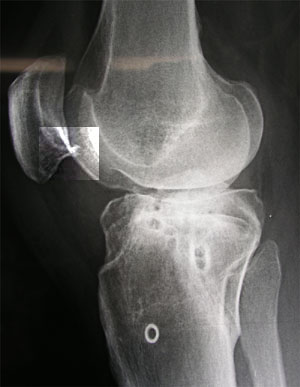

In diesem Röntgenbild (für einmal von der anderen Seite aufgenommen) von Anfang Dezember 2002 (Inselspital Bern, anlässlich der Punktion - aufs Bild klicken für grössere Fassung) sieht man wiederum schön den mutmasslichen Osteophyten an der Patella, den ich immer mehr für die Schmerzen verantwortlich mache, die nunmehr seit einem halben Jahr andauern.

Hier ist eine Ausschnittsvergrösserung der unteren Patellareagion zu sehen (im Bild oben eingerahmt).